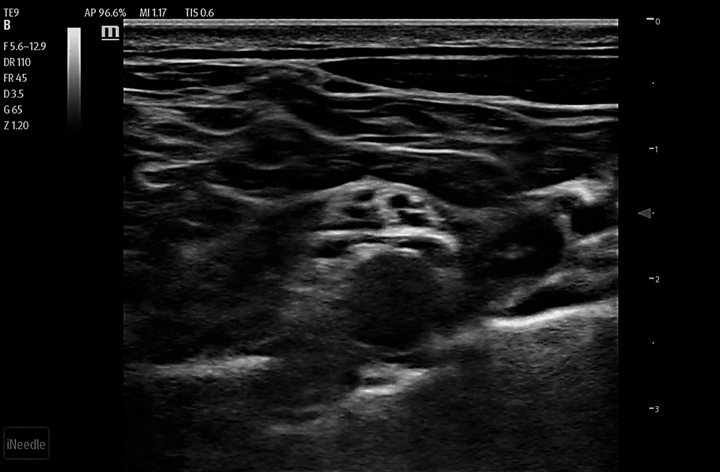

Needle Guidance